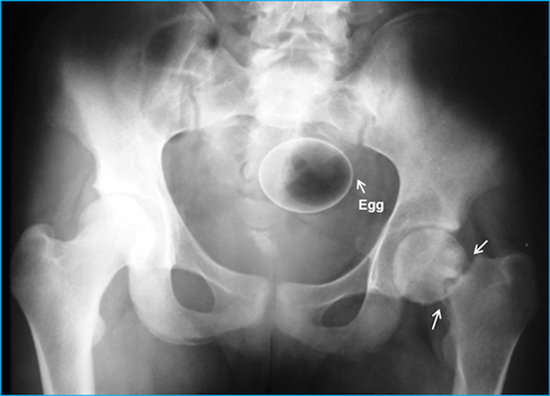

มาดูภาพเอกซเรย์ สารพัดสิ่งของที่เคยหลุดเข้าทวารหนัก

เผยภาพเอกซเรย์สุดอึ้ง สารพัดสิ่งที่เคยหลุดเข้าไปภายในทวารหนักผู้ป่วยทั่วโลก แปลกพิสดารกันจริง ๆ

การยัดสิ่งของต่าง ๆ เข้าไปในทวารหนักนั้น ไม่ว่าจะด้วยเหตุผลเพื่อหลบซ่อนการตรวจของเจ้าหน้าที่ทางการ หรือเป็นความผิดพลาดจากการแก้ขัดเมื่อเกิดอารมณ์ทางเพศก็ตาม สิ่งของที่หลุดเข้าไปนั้นล้วนแล้วแต่สร้างอันตรายให้กับอวัยวะภายในของผู้ป่วยได้หมด แต่ถึงจะเป็นอย่างนั้น เคสทางการแพทย์ว่าด้วยเรื่องของสิ่งแปลกปลอมที่หลุดเข้าไปในทวารหนักก็ยังมีให้เห็นอยู่เรื่อย ๆ ถมเถ แต่ละอย่างทำเอาอึ้ง ทึ่ง แบบไม่คิดว่ามันจะหลุดเข้าไปในทวารหนักได้จริง ๆ ดังเช่นตัวอย่างเคสที่เรานำมาฝากกันในวันนี้..

ไข่ไก่